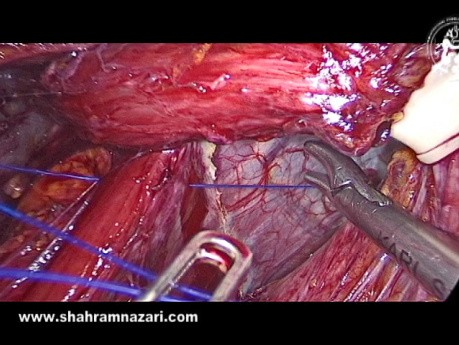

OrthoProcédure - Arthroplastie de la Tête Radiale

OrthoProcédure - Arthroplastie de la Tête Radiale.

Shahram Nazari

PU-PH